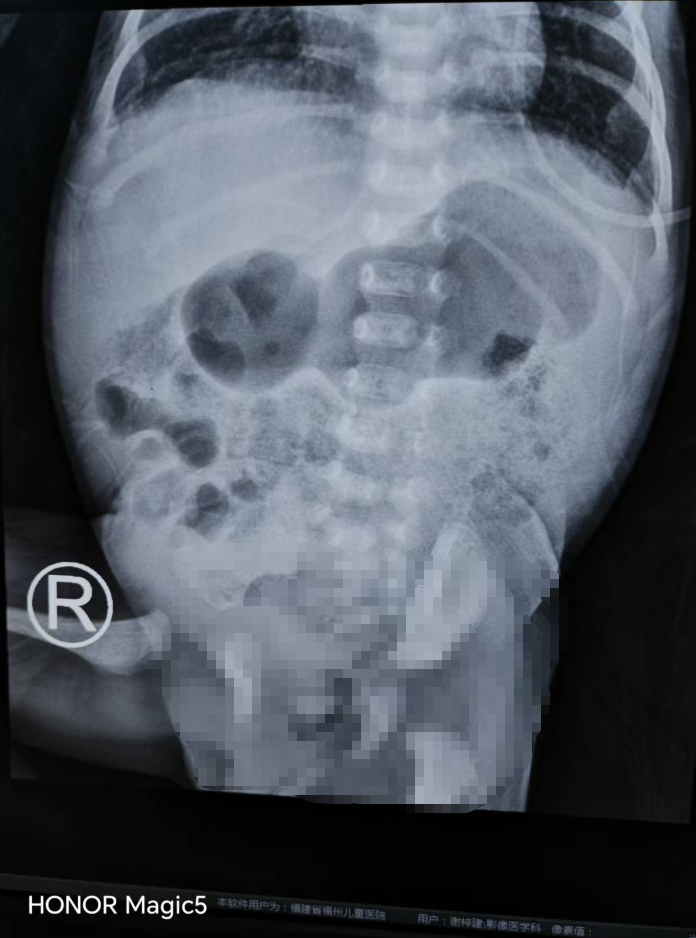

患儿腹平片-不全性高位肠梗阻